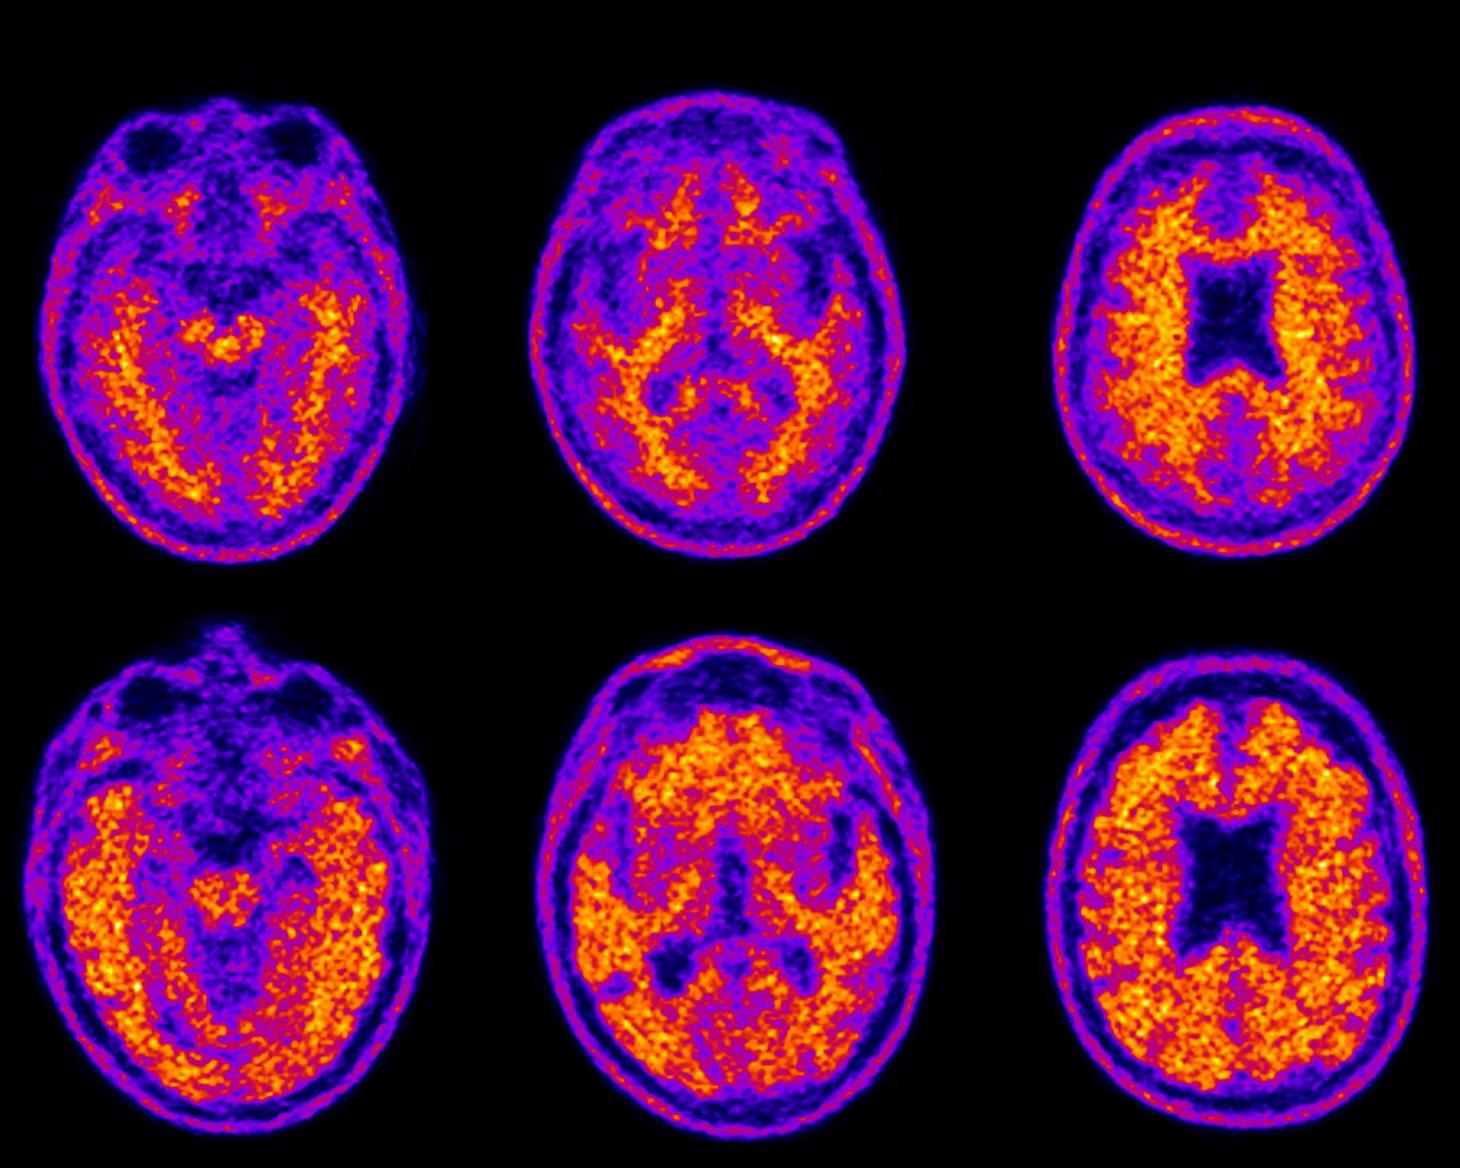

This demolishes the brain toxin that causes Alzheimer’s Daily Medical

This demolishes the brain toxin that causes Alzheimer’s Daily Medical Types Of Brain Plaques Diffuse plaques and neuritic plaques. We’ve got two main types: Here, we review the current knowledge about neuritic plaques, a subset of aβ plaques surrounded by swollen or dystrophic neurites, which represent the most detrimental. Cerebral arteriosclerosis is a disease that occurs when the arteries in the brain become hard, thick, and narrow due to the. In fact, glial cells. Types Of Brain Plaques.